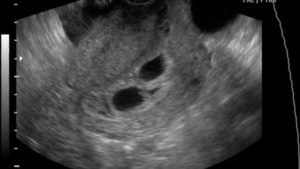

Следовательно, наличие двойняшек в утробе выявляется посредством ультразвука уже через месяц после зачатия, на снимке они выглядят как 2 образования темного цвета внутри полости матки (см. фото УЗИ-обследования двойни ниже).

• УЗИ-диагностика двойни через 11 недель показывает немного уменьшенные для своего срока развития размеры первого и второго плода – примерно 4,2-4,8 см.

• При обследовании на 12 неделе эмбрионы имеют длину по 6 см, а их вес составляет примерно 8 грамм.